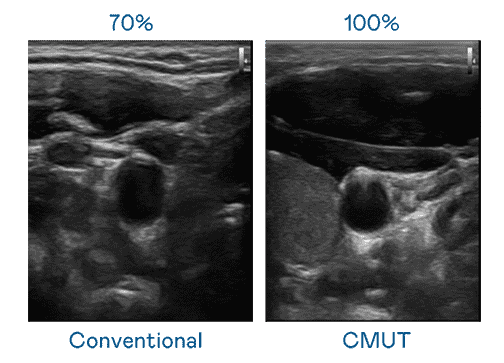

CMUT 技术是一种用电容式微机电元件来产生超音波讯号的技术。。。。与传统 PZT 压电式技术相比,,,CMUT 频宽增加 30%,,,更宽频的超音波讯号让影像解析度大幅提升,,,是实现高影像品质医疗超音波扫描、、、促进精准医疗发展的关键技术。。。

大频宽带来超清晰影像

超音波影像的解析度高低,,首先取决于探头能发出的讯号频宽。。Wepay CMUT 可提供高清晰的超音波讯号,,提供高频宽、、高灵敏度、、、、影像纹理细节更高的超音波影像,,协助医护人员缩短影像判读时间及利用精准的医疗影像进行诊断。。。